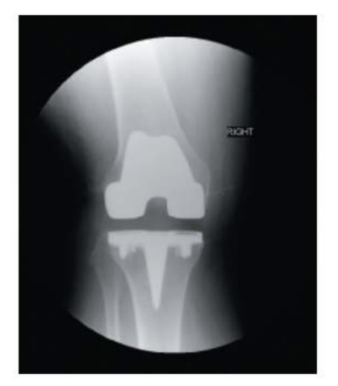

<p>The x-ray of the right knee above shows a total knee replacemnet with prosthesis implant. What view is this presentation?</p>

The x-ray of the right knee above shows a total knee replacemnet with prosthesis implant. What view is this presentation?

coronal